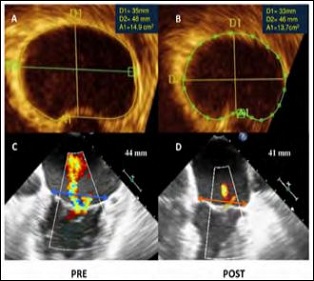

The Atrial Flow Regulator (AFR) device (Occlutech, Helsingborg, Sweden) (Figures 2A and 2B, Supplementary Table 1) with an 8-mm fenestration, 5-mm height and 21-mm discs diameter was implanted into the interatrial septum (Figure 3). Postoperative TEE showed left-to-right interatrial shunting through the device (Figure 4), significantly reduced mitral annular area and trivial residual mitral regurgitation (Figure 5). Post-procedural right heart catheterization demonstrated a drop in PCWP (12 mmHg), an increase in RA and a 1.2 QP/QS ratio (Table 1). At 3-months follow-up the patient was asymptomatic (NYHA I), BNP decreased to 380 ng/L and the 6MWT distance increased to 470 m. TTE showed AFR patency, mild mitral regurgitation (Figure 6, Supplementary Movie 1, B), moderate tricuspid regurgitation with mildly enlarged but normally functioning right ventricle.

Figure 5: Pre and Postoperatively 3D TEE (A-B) measurement of dimensions and area of the mitral anulus and 2-D color-Doppler (C-D) assessment of mitral regurgitation.

Note: Blue line: pre-procedure mitral annulus dimension; Orange line: post-procedure mitral anulus dimension

In our patient variations in surrogate parameters seen 3-month after the procedure are consistent with those observed in published studies: NYHA class decrease from II to I, BNP decreased by 3.9% [mean 2,8% pro BNP decrease (p=0.25)] was observed in patients with HFpEF in the AFR PRELIEVE trial [7], and the 6MWT distance increased by 29% [mean 17% 6MWT distance increase (p=0.01)] was observed in a single-arm open-label study using the V-wave system in patients with both HFrEF and HFpEF) [6]. In our case a marked reduction in mitral annular area was documented after AFR implantation as a likely consequence of reduction in LA volume. This may determine a reduction in MR severity triggering an hemodynamic virtuous circle.